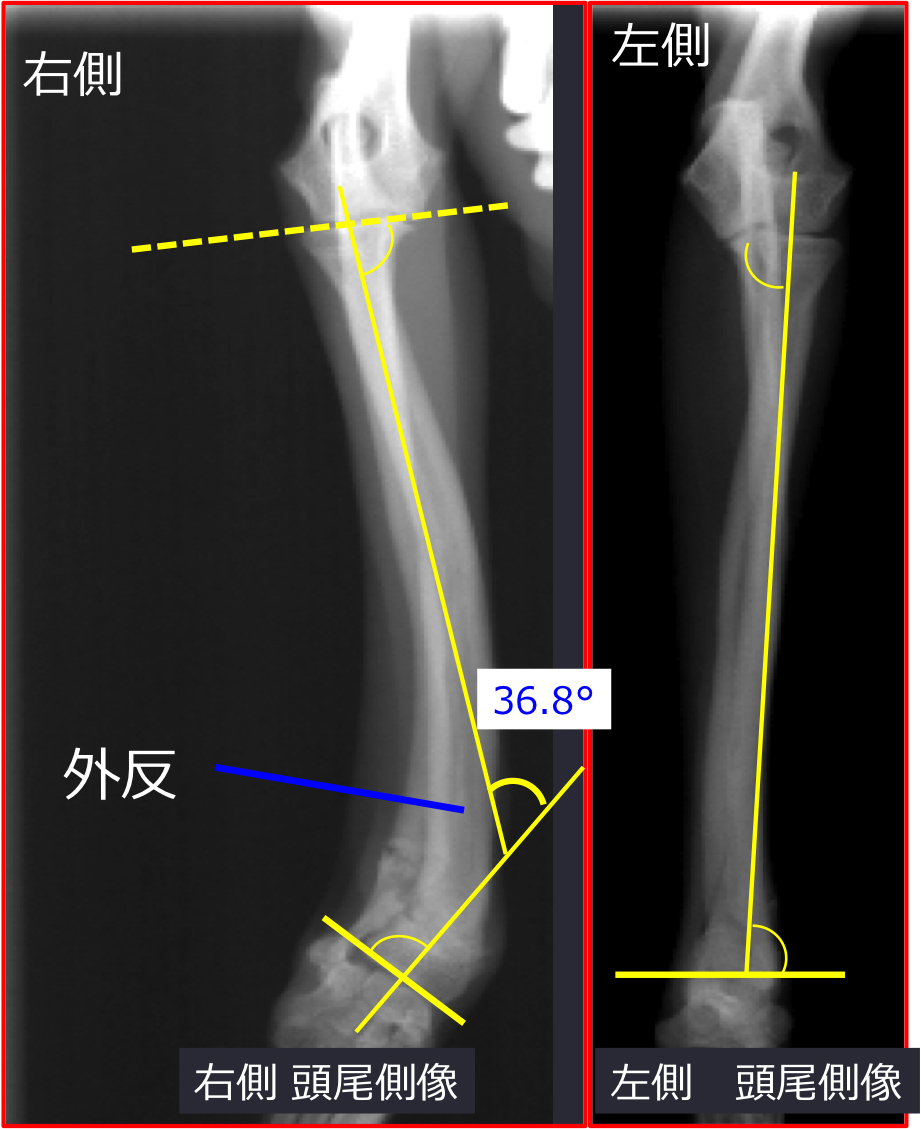

<模擬手術>

1. 変形矯正を計画

・側面像(矯正前26.8°を17.6°へ)

・正面像にて(矯正前36.8°を3.5°へ)

http://www.atpress.ne.jp/releases/54567/img_54567_5.jpg